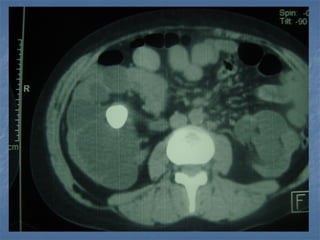

TAC renal sin contraste

Litiasis renal  Pacientevarón  Edad : 62 años  Antecedente : Se le ha efectuado 8 sesiones previas de ESWL hace 1 año en Lima con resultados negativos  Diagnóstico : Litiasis en unión pieloureteral izquierda de 2.5 cm. de diámetro mayor + Litiasis en cáliz inferior izquierdo de 0.8 cm.

TAC renal sincontraste

1 1 Mean /SD : 1468.8/53.1